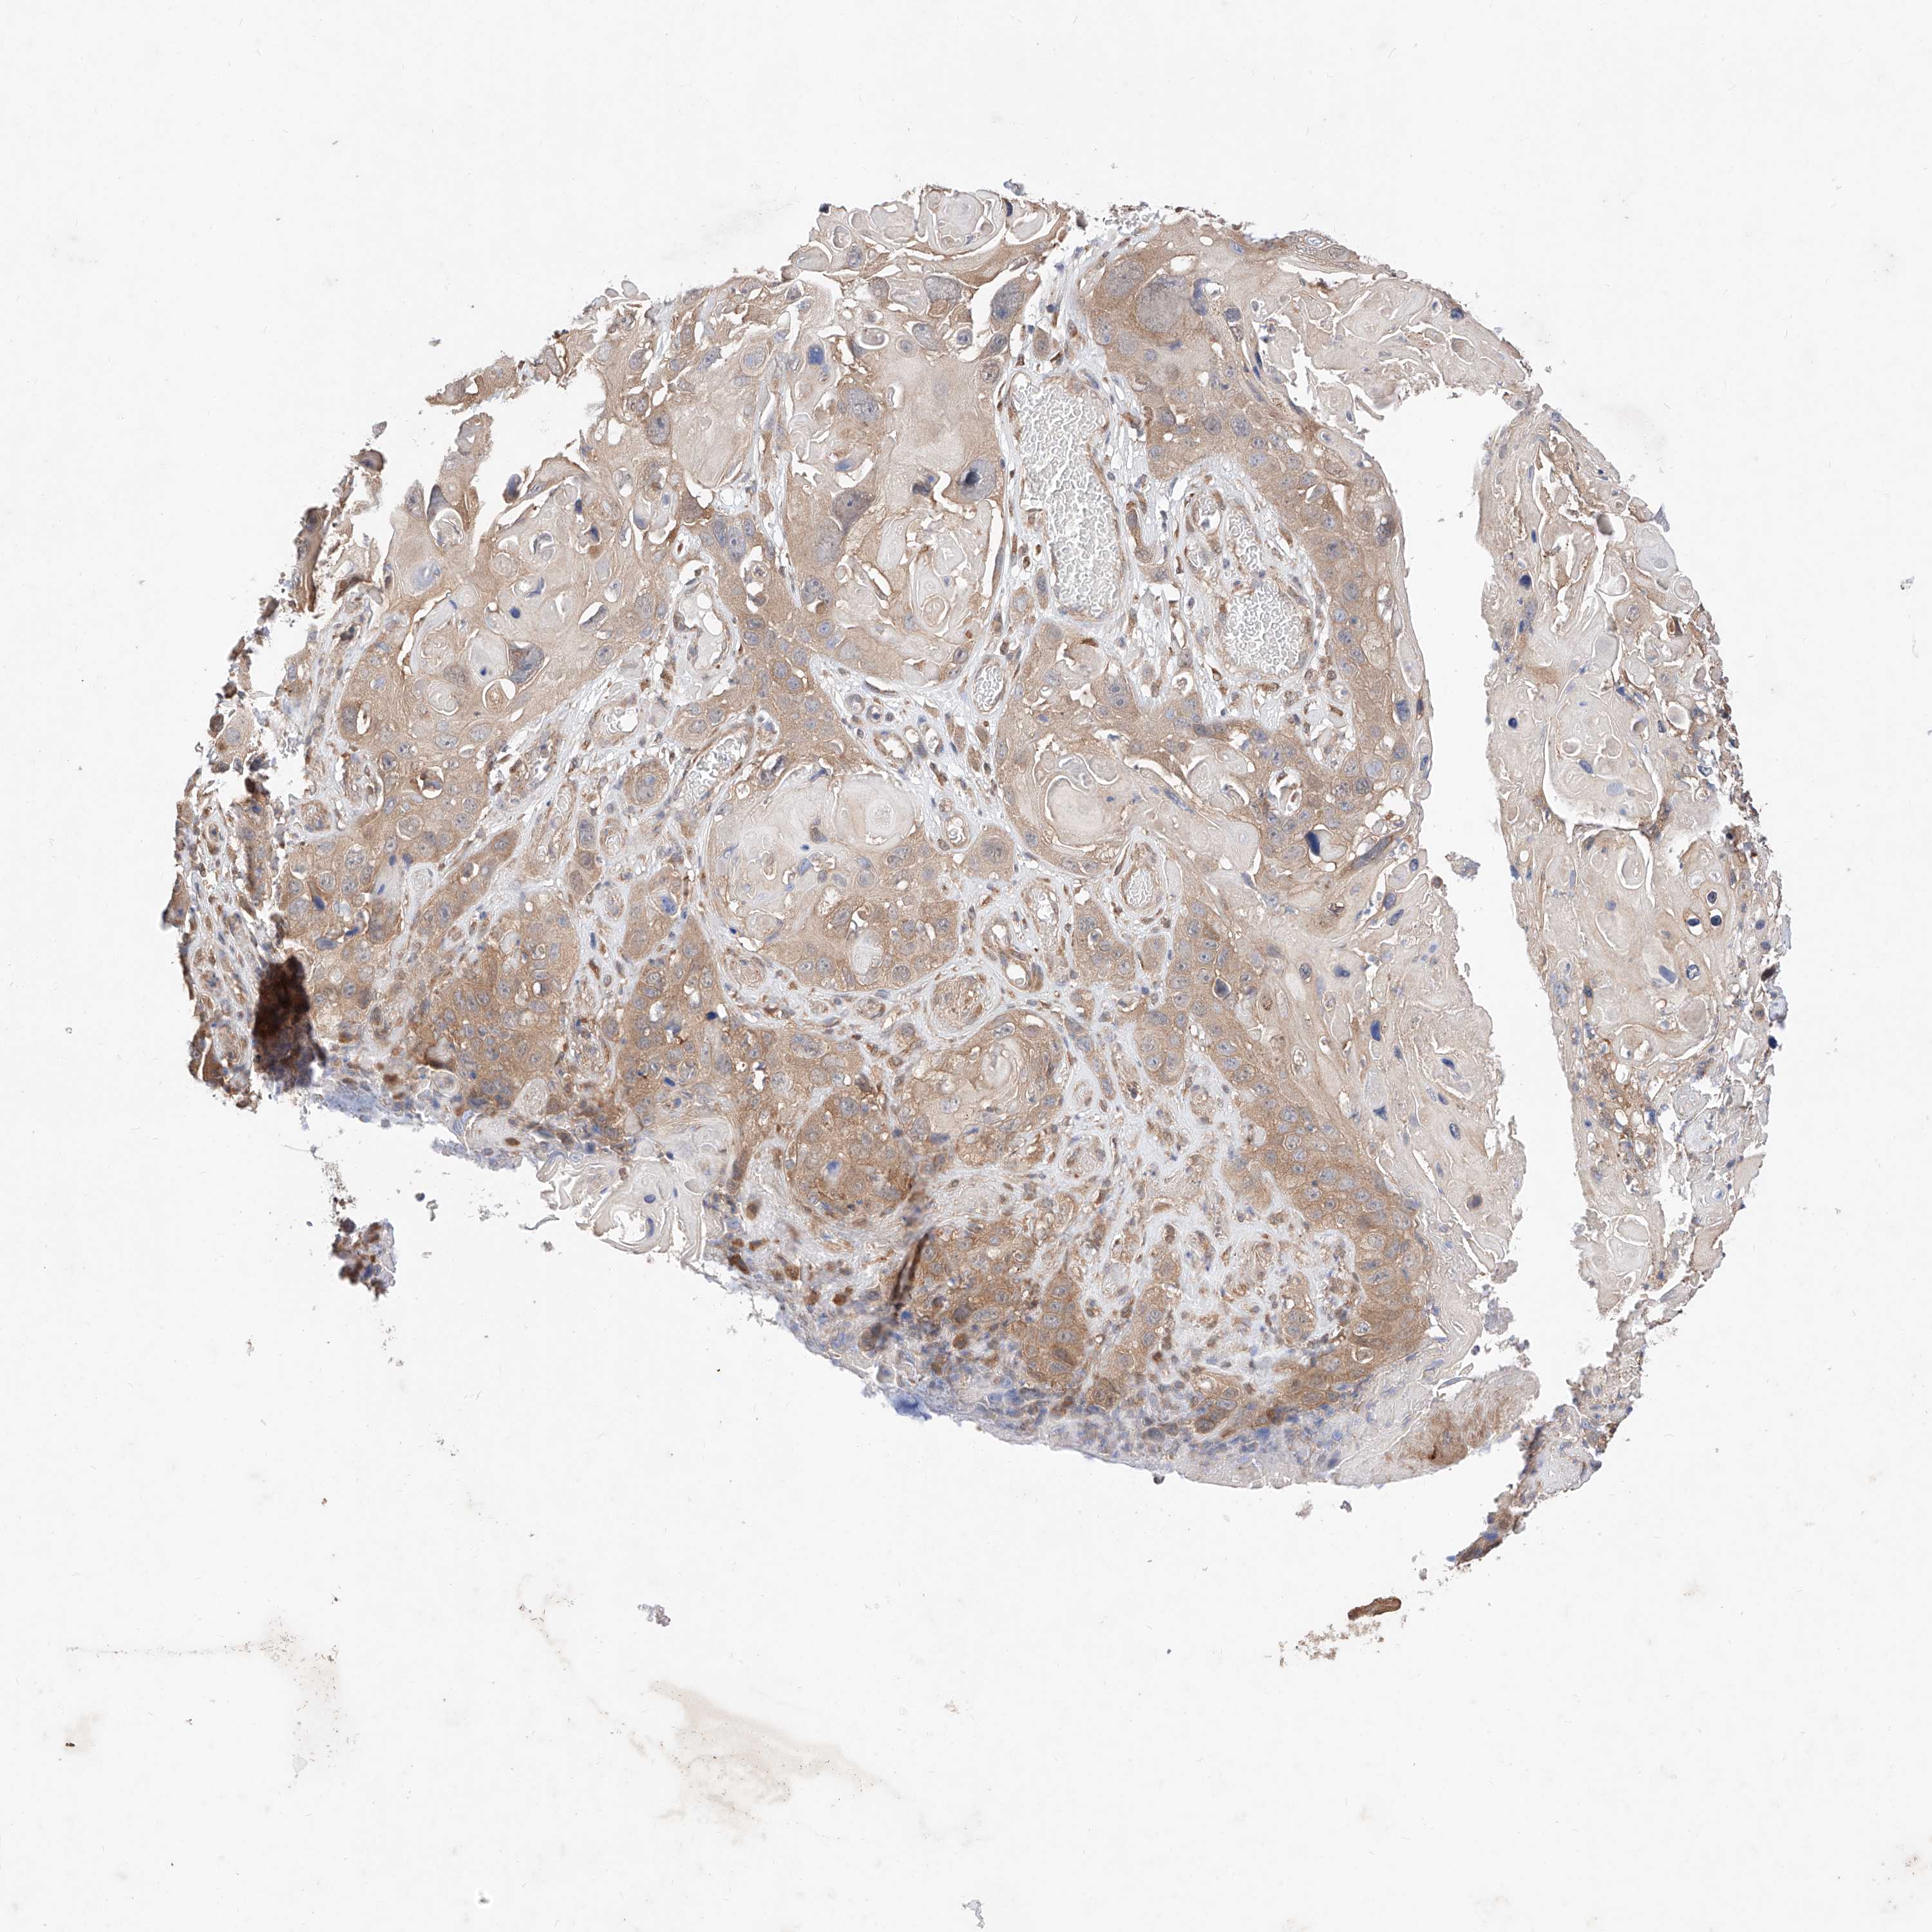

SKIN CANCER - Protein expressioni

A mouse-over function shows sample information and annotation data. Click on an image to view it in a full screen mode. Samples can be filtered based on level of antibody staining by selecting one or several of the following categories: high, medium, low and not detected. The assay and annotation is described here.

Antibody stainingi

Antibody staining in the annotated cell types in the current human tissue is reported as not detected, low, medium, or high, based on conventional immunohistochemistry profiling in selected tissues. This score is based on the combination of the staining intensity and fraction of stained cells.

Each image is clickable and will lead to virtual microscopy that enables deeper exploration of all samples and also displays staining intensity scores, fraction scores and subcellular localization as well as patient and tissue information for each sample.

Antibody HPA006491

Staining

High

Medium

Low

Not detected

Intensity

Strong

Moderate

Weak

Negative

Quantity

>75%

75%-25%

<25%

None

Location

Nuclear

Cytoplasmic/membranous

Cytoplasmic/membranous,nuclear

Basal cell carcinoma